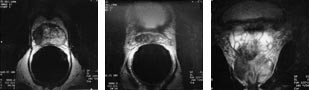

Innvekst i sædblærene viser seg i T2-vektede bilder som fortykkelse av de hypointense veggene og utfylling av hulrommene i sædblærene med hypointenst tumorvev (fig 6). Væsken i sædblærene er normalt sterkt hyperintens. Dette gir en optimal bakgrunn for fremstilling av tumorvekst i sædblærene. Dilatasjon av sædblærene på grunn av obstruerende infiltrasjon av tumor i ductuli ejaculatorii kan også påvises.

Man har hatt problem med å etablere robuste kriterier for både kapselgjennomvekst og innvekst i sædblæren (fig 4, 5). Kriterier som glatt konturdeformitet, fortykkelse av kapselen og stripeformet økt tetthet (stranding) i det periprostatiske fettvevet er upålitelige for prediksjon av kapselgjennomvekst (18). Irregulær konturdeformitet, tumorvev i den rektoprostatiske vinkel og asymmetri av de nevrovaskulære buntene ved prostatas laterale hjørner er sannsynligvis de beste kriteriene (tab 3). En stor andel av disse svulstene viser kun spredning av mikroskopiske tumorfoci (< 1 mm) til det ekstraprostatiske vevet ved den histopatologiske undersøkelsen av operasjonspreparatet; 43 % i vår studie (19). Ingen radiologisk metode har høy nok oppløselighet til å påvise en slik form av spredning.